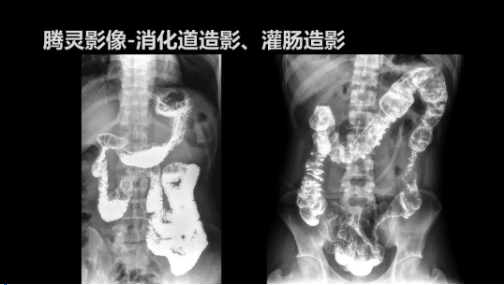

“騰靈”是安健科技的第四代動(dòng)態(tài)DR產(chǎn)品,可實(shí)現(xiàn)全科室應(yīng)用。如各類常規(guī)的X線檢查、消化道檢查、骨科檢查、婦科、兒科檢查等。此外,安健科技為“騰靈”在真正意義上實(shí)現(xiàn)多科室、多功能診斷進(jìn)行了多項(xiàng)針對(duì)性設(shè)計(jì)。

此外,“騰靈”為了能夠幫助醫(yī)生更快速、有效的定位病灶,還增加了多項(xiàng)精準(zhǔn)診斷保障功能,如支持動(dòng)態(tài)觀察診斷,實(shí)時(shí)高清點(diǎn)片等?!膀v靈”透視切換高清點(diǎn)片曝光,捕捉關(guān)鍵病灶診斷僅需0.8s,同時(shí)還支持圖像局部放大,醫(yī)生可自由切換15’12’和9’三種放大模式,另外,“騰靈”還支持視頻保存、回放功能,幫助醫(yī)生在檢查結(jié)束后通過(guò)回放查看細(xì)節(jié),為醫(yī)生的診斷增加信心。